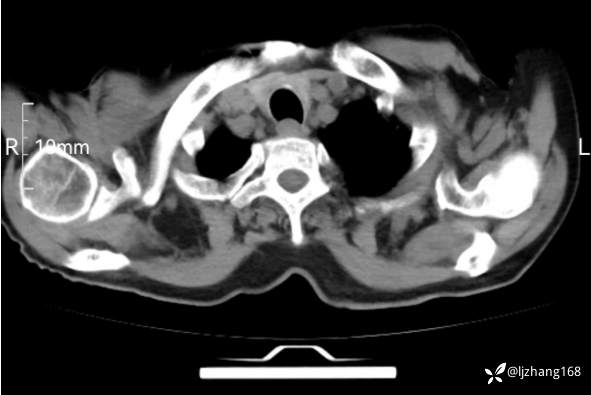

辅助检查:胸部CT:双肺肺气肿,间质性病变,血气分析:PH 7.413, PCO2 29.2mmHg, PO2,81.8mmHg,乳酸 3.3mmol/1,剩余碱-4.0mmol/1,HC03 18.8mmol/1。全血超敏C反应蛋白:超敏C反应蛋白 135.60 mg/L、 白细胞 14x19^9/L,中性粒细胞11.6x10^9/L。